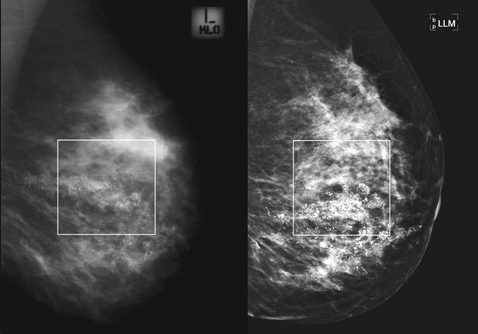

Normal Mammo Image versus 3D Image:

Film versus Digital Image: